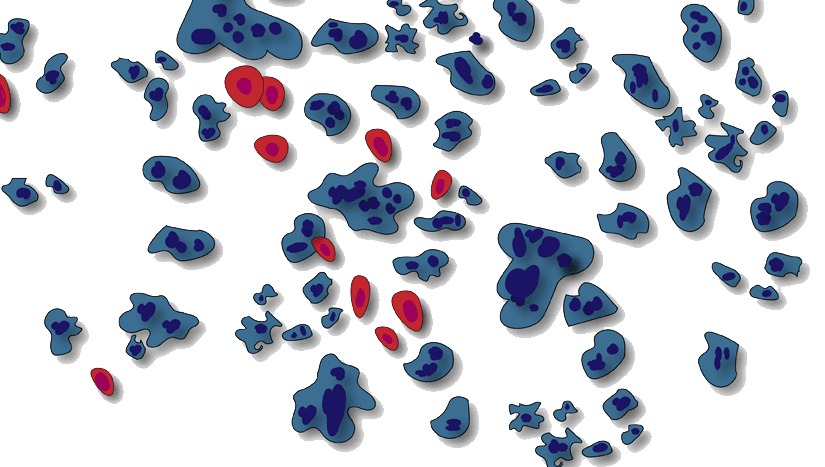

Stammzellen haben ein großes Potential die Immunzellen, die bei einem Defekt eine Entzündung - und damit den Schmerz - auslösen, zu hemmen. Hierdurch kann die Entzündung unterbunden werden und der Schmerz lässt - häufig sofort - nach. Nachfolgend können die Stammzellen die Regeneration des Gewebes anregen und so weitere Schädigungen unterbinden und eine Heilung fördern. Ja nach individueller Problematik kann so der Schmerz ursächlich behandelt, die Regeneration beschleunigt oder ein Gelenkersatz aufgeschoben werden.

Der Einsatz von Stammzellen bei der Behandlung von Knieproblemen hat zwei Hauptziele: die Bekämpfung der Ursache Ihrer Schmerzen und die Förderung der Regeneration. Durch eine natürliche, örtlich gebundene Hemmung der Immunreaktion stoppt oder vermindert die Stammzellen-Injektion die entzündliche Immunreaktion im Knie. Da diese, vor allem in frühen Stadien, oft die eigentliche Ursache für Schmerzen ist, kann so eine sofortige oder sehr schnelle Abmilderung des Schmerzes bis hin zur kompletten Schmerzfreiheit des Knies erzielt werden.

Bei degenerativen Erkrankungen wie Arthrose und Arthrits kann nach der Hemmung der Entzündung durch die Stammzellen die Regeneration gerfördert werden und so eine Verlangsamung des Fortschreitens erreicht werden. Eine vollständige Heilung ist derzeit mit keiner weltweit verfügbaren Therapie möglich. Bei Rissen oder Dehnungen der Bänder und Sehnen sowie nach Operationen zur Wiederherstellung von Bändern können die Stammzellen die Abheilung fördern und so eine schnelle Rehabilitation unterstützen.